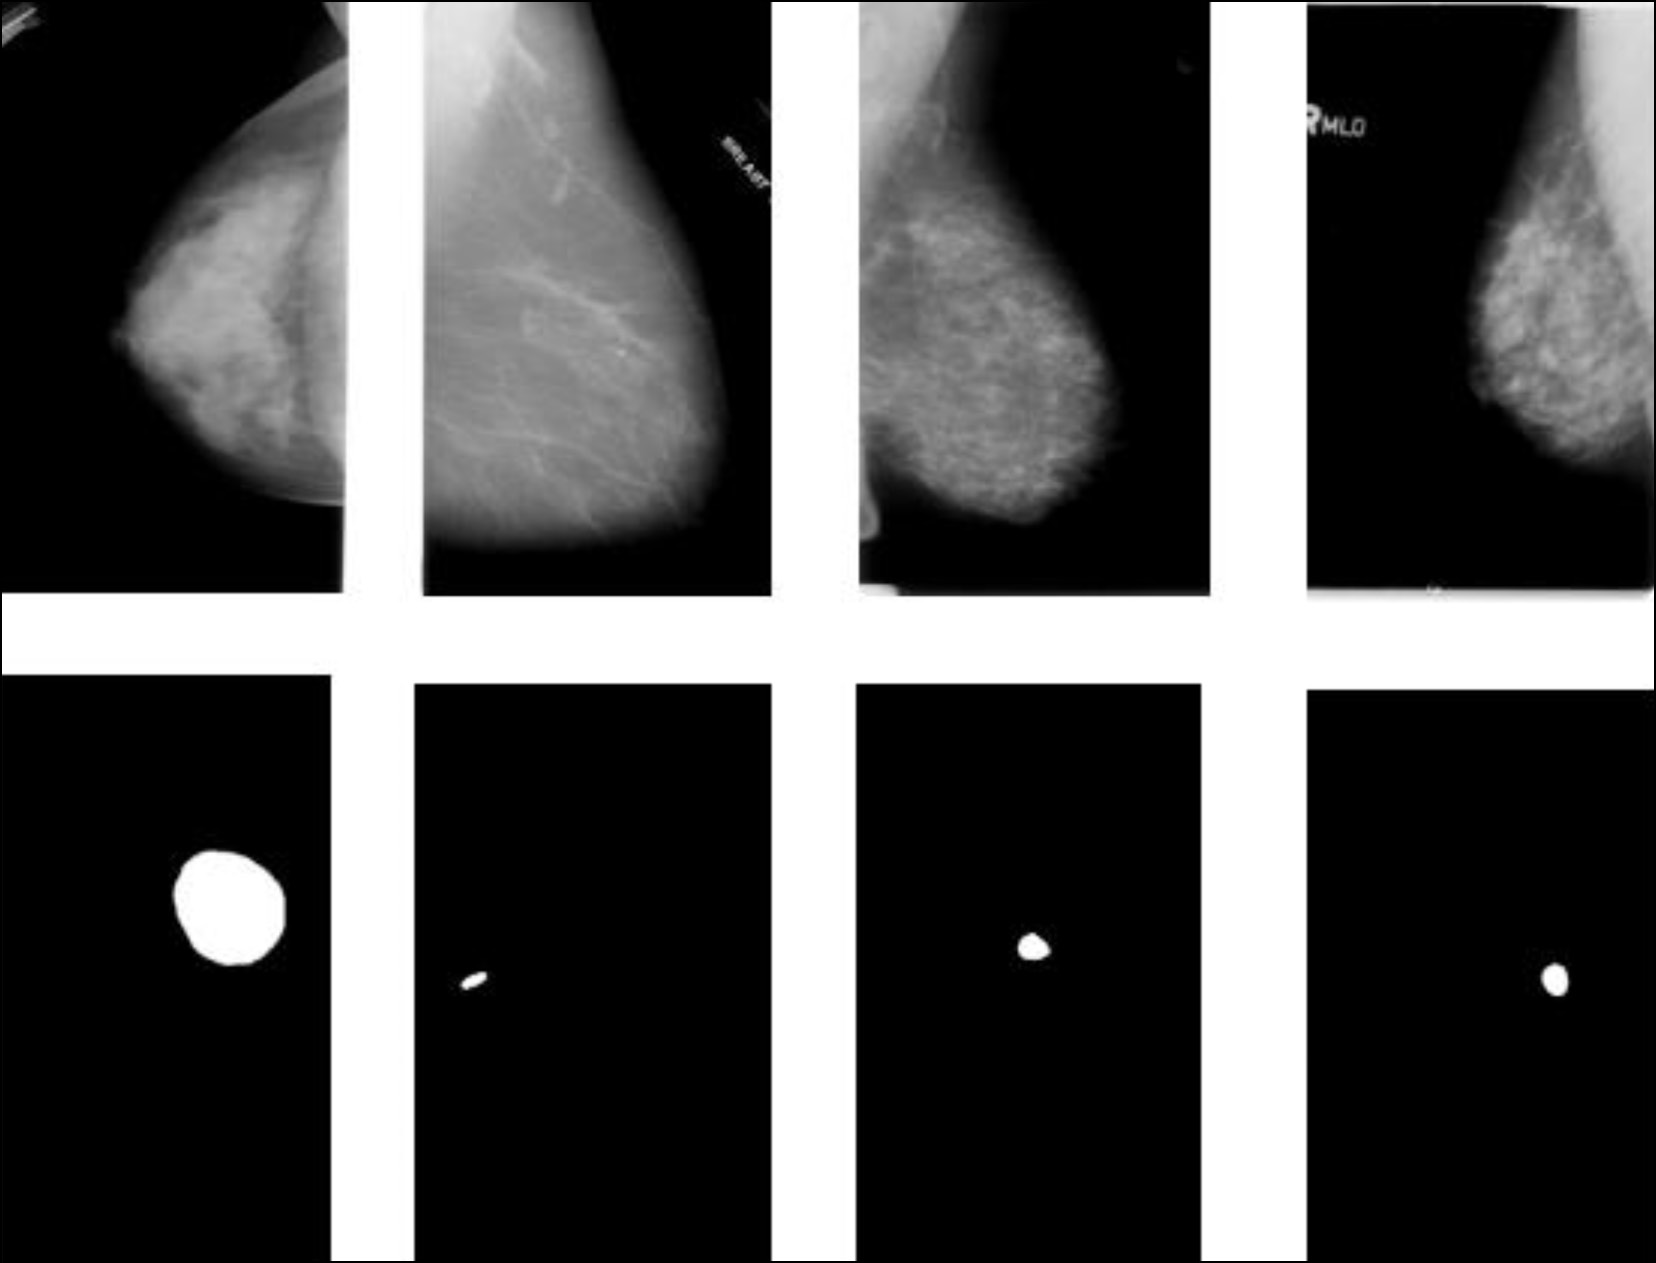

- Raza S.K., Sarwar S.S., Syed S.M., Khan N.A. Classification and Segmentation of Breast Tumor Using Mask R- CNN on Mammograms // Research Square. 2021. doi: 10.21203/rs.3.rs-523546/v1

- Tsochatzidis L., Costaridou L., Pratikakis I. Deep Learning for Breast Cancer Diagnosis from Mammograms – A Comparative Study // Journal of Imaging. 2019. Vol. 5, N 3. P. 37. doi: 10.3390/jimaging5030037

- Ручай А.Н., Кобер В.И., Дорофеев К.А., и др. Классификация патологий молочной железы с использованием глубокой сверточной нейронной сети и трансферного обучения // Информационные процессы. 2020. Т. 20, № 4. С. 357–365.

- Сасов Д.А., Зубков А.В., Орлова Ю.А., Турицына А.В. Классификация рака молочной железы с помощью сверточных нейронных сетей // Инженерный вестник Дона. 2023. № 6. С. 730–741.